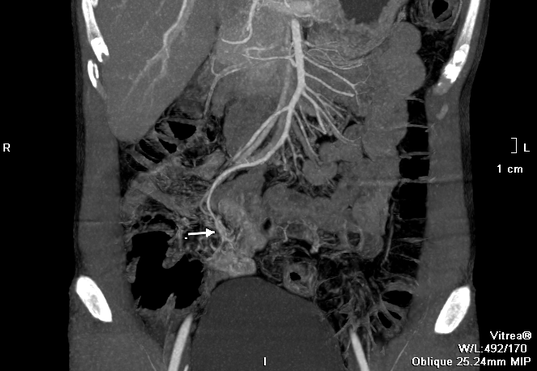

Sau khi hồi sức tích cực, chụp cắt lớp ổ bụng, các bác sĩ phát hiện búi dị dạng mạch máu từ một nhánh của động mạch mạc treo tràng trên, nằm ngay trên thành ruột non đang có dấu hiệu chảy máu.

Hình ảnh CT của bệnh nhân khi vào viện. (Ảnh: BVCC)

Bệnh nhân được hội chẩn, điều trị khẩn cấp bằng phương pháp can thiệp mạch để nút búi dị dạng. Các bác sĩ đã luồn một ống thông đường kính 1mm vào chính xác vị trí chảy máu nút mạch cứu bệnh nhân. Sau 1 ngày điều trị, bệnh nhân không còn triệu chứng chảy máu, sức khỏe dần phục hồi.